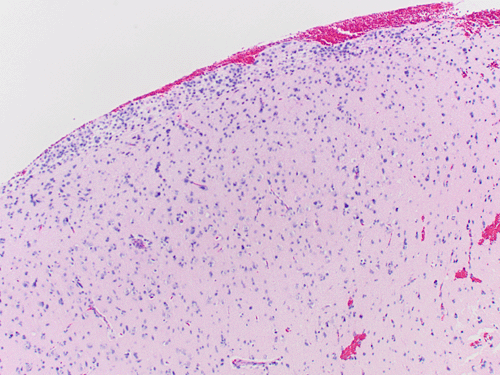

Clinical information: The patient was a 40 year-old man with a history of headache for months and suddenly develop nausea and vomiting in the morning. MRI demonstrated a diffusely infiltrative, non-enhancing lesions that dominated the right frontal lobe with extension across the genu of the corpus callosum into the left frontal region. The lesion also extended in occipital direction to the right basal ganglia, sub-insular region, and anterior temporal lobe. A resection was performed. The followings are representative images:

MRI Axial